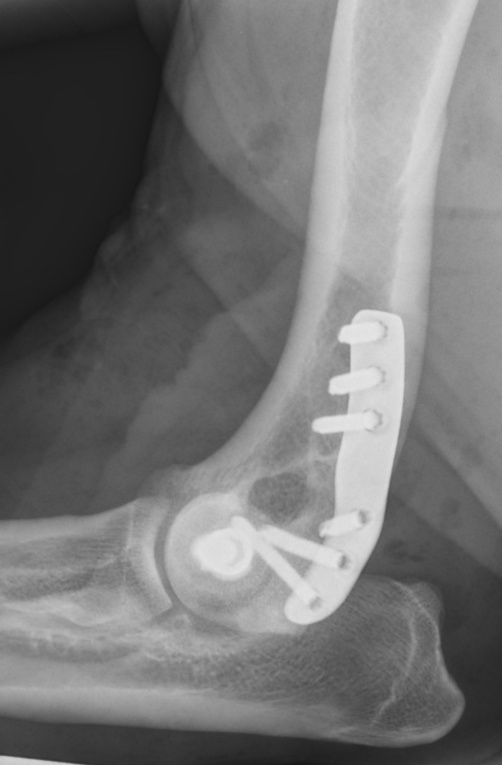

These fractures need to be re-aligned as accurately as possible, within a few days of occurring, to try and optimise elbow function in the long term. They are generally stabilised using a screw across the condyle, and a plate and screws running up the side of the bone. Sometimes, the plate is not used and more screws or a bone pin is used instead. Movement Specialist, Ben Walton, helped to design and develop a system of anatomic bone plates for humeral condylar fractures.

- What implants are used. The best-available published reports suggest that complication rates are lower when plates are incorporated into the repair.

Jones RL, Tomlinson AW, Barnes DM, Hood RS, Ogden DM, Owen MA, Onyett JR, Walton MB

Clinical assessment of a lateral epicondylar anatomical plate for the stabilisation of humeral condylar fractures in dogs. BVOA Autumn Meeting, 2021, Nottingham.